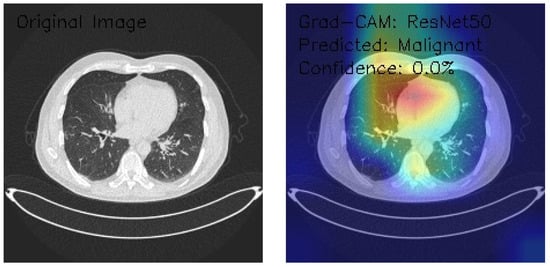

Analysis of InceptionV3 Model Performance on Lung CT Images with Grad-CAM Visualization

The results section of this study presents the detailed findings from an advanced analysis of three axial chest CT images processed using the InceptionV3 deep learning model. This analysis leverages the sophisticated capabilities of Grad-CAM to provide a comprehensive visualization of the regions within the CT images that the model identifies as significant for its predictions. Combining the robust classification performance of the InceptionV3 architecture with the interpretability offered by Grad-CAM, this approach not only evaluates the model’s predictive accuracy but also elucidates the spatial patterns of attention within the medical imaging context. This dual focus allows for a deeper understanding of the diagnostic potential of deep learning in radiology and the interpretive transparency essential for clinical application. The following results detail these observations, highlighting key insights into the model’s behavior and implications for automated diagnostic processes.

Figure 9 shows that the CT image reveals clear lung fields with well-defined bronchial structures, indicating no abnormalities in the original scan. The Grad-CAM visualization highlights a distinctive rainbow-like activation pattern, predominantly focusing on the central and bilateral lung fields with symmetric intensity. Despite these detailed attention patterns, the model classifies the image as Normal with a confidence score of 0.0%, pointing to significant issues in confidence calibration. This suggests the model can identify relevant anatomical regions but lacks reliability in translating these insights into confident and actionable classifications. Further calibration and optimization are necessary for clinical applicability.

Figure 9.

Grad-CAM visualization using InceptionV3 for lung CT scan with normal prediction. (Source: author’s analysis from data, 2024).

Figure 10 shows that the CT image analysis highlights scattered nodular opacities, suggesting potential abnormalities. The Grad-CAM visualization indicates peripheral activation patterns, with a notable focus on lateral lung regions. The heatmap’s color gradients suggest varying feature importance across these areas. Despite identifying relevant features, the model classifies the image as Malignant with a confidence score of 0.0%, reflecting significant uncertainty. This indicates a disconnect between the model’s feature detection and its confidence in classification, emphasizing the need for recalibration and potential retraining to enhance diagnostic reliability and decision-making accuracy.

Figure 10.

Grad-CAM visualization with InceptionV3 for lung CT image analysis reveals scattered nodular opacities, indicating possible abnormalities. (Source: author’s analysis from data, 2024).

Figure 11 shows that the CT image displays interstitial patterns, indicative of potential structural abnormalities. The Grad-CAM visualization highlights strong activation centrally and in the right lung, with an asymmetric attention distribution favoring the right hemithorax. Despite this focused feature analysis, the model classifies the image as Normal with a confidence score of 0.0%, suggesting significant limitations in the model’s confidence calibration and decision-making reliability. The mismatch between observed features and classification confidence underscores the need for model refinement, particularly in aligning activation insights with robust, actionable predictions.

Figure 11.

Grad-CAM visualization using InceptionV3 for lung CT scan with malignant prediction. (Source: author’s analysis from data, 2024).

This analysis evaluates three axial chest CT images processed by an InceptionV3 model with Grad-CAM visualizations, focusing on attention regions and classification outcomes. Image 1 shows clear lung fields with symmetric central activation, classified as Normal with 0.0% confidence. Image 2, with scattered nodular opacities, displays peripheral activation patterns and is classified as Malignant, again with 0.0% confidence. Image 3 exhibits interstitial patterns with strong central and right-sided activation, also classified as Normal with 0.0% confidence. The Grad-CAM visualizations highlight relevant anatomical features, but the model’s uniform low confidence scores reveal calibration and classification inefficiencies. Recommendations include the recalibration of confidence scoring, fine-tuning classification layers, and integrating ensemble methods. While feature detection appears robust, these refinements are critical for clinical reliability and decision-making.